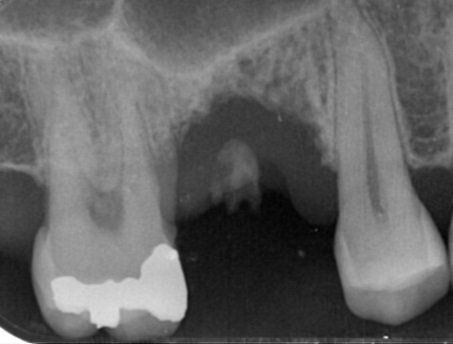

Trattamenti di endodonzia

L'endodonzia è quella branca dell'odontoiatria che si occupa della terapia dello spazio all'interno del dente che contiene la polpa dentaria, costituita da cellule, vasi e nervi. La terapia endodontica è indispensabile quando una lesione cariosa o traumatica al dente abbia determinato un'alterazione non reversibile del tessuto pulpare.

Presso lo studio Duchi, impieghiamo due tecniche endodontiche: la terapia ortograda, quando è possibile operare attraverso il dente lungo i canali radicolari (terapia canalare o devitalizzazione) e la terapia retrograda, più comunemente indicata come endodonzia chirurgica (apicectomia), per i casi in cui non è possibile passare lungo i canali radicolari, per la presenza di ostacoli di varia natura.

prima e dopo...